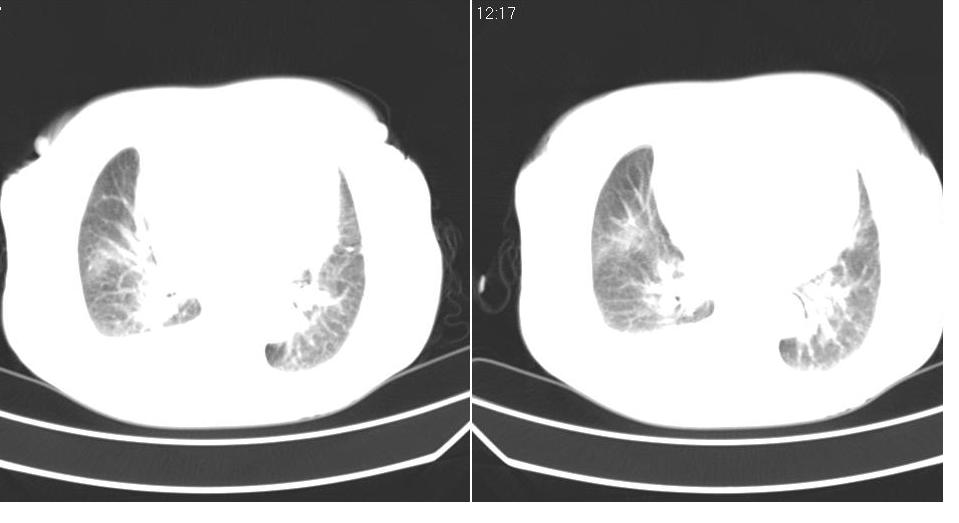

以下是引用liaizhi在2007-7-11 15:41:00的发言:[br]两肺纹理增粗,肺门影增大,气管支气管通畅。升主动脉壁及冠状动脉壁钙化。左房左室稍扩大。心包积液,胸腔积液。考虑冠心病并心功能不全,肺水肿,胸腔积液。

以下是引用zhangzhongshou在2007-7-11 13:16:00的发言:[br]1、冠状动脉钙化[br]2、心包积液[br]3、右侧胸腔积液[br]大家都考虑心衰,冠状动脉钙化、肺纹理增强,胸腔积液、心包积液,表面上是支持,但是为什么右侧有较多积液,左侧没有呢? 如果用结核性胸膜炎,并结核性心包炎也可解释,请楼主进一步提供临床资料。

以下是引用zrs在2007-7-11 14:40:00的发言:[br]支持心衰,心衰所至的胸腔积液常常是右侧多